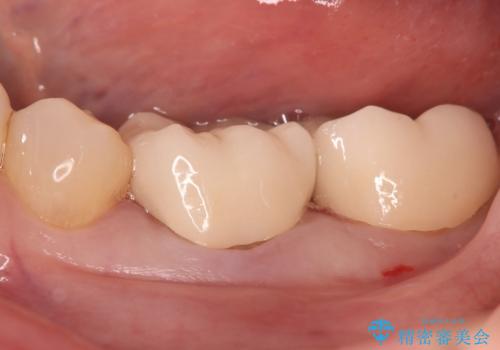

- ご友人との会話中などに、下の歯に入れてあるメタルインレーが見えてしまうのが気になり、やり変えを希望された患者様です。審美性、清掃性に優れたセラミックでの治療を希望されたため、セラミックインレー、クラウンで治療いたしました。

口を開けた際の見た目が向上し、非常に満足いただけました